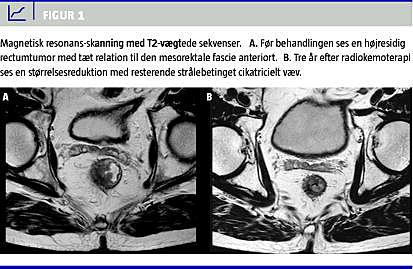

Patienten ønskede efter radiokemoterapien ikke at gennemføre operationen, idet han alligevel ikke ville kunne acceptere en stomi. Han indvilligede dog i et kontrolforløb, og blev indkaldt ca. hvert halve år til en klinisk undersøgelse, sigmoideoskopi/koloskopi inklusive biopsi, MR-skanning og computertomografi, hvor man fortsat så regression af patientens cancer. Efter et år kunne der udelukkende påvises arvæv, og tilstanden forblev stationær, også ved seneste kontrol i november 2009 (Figur 1 ).